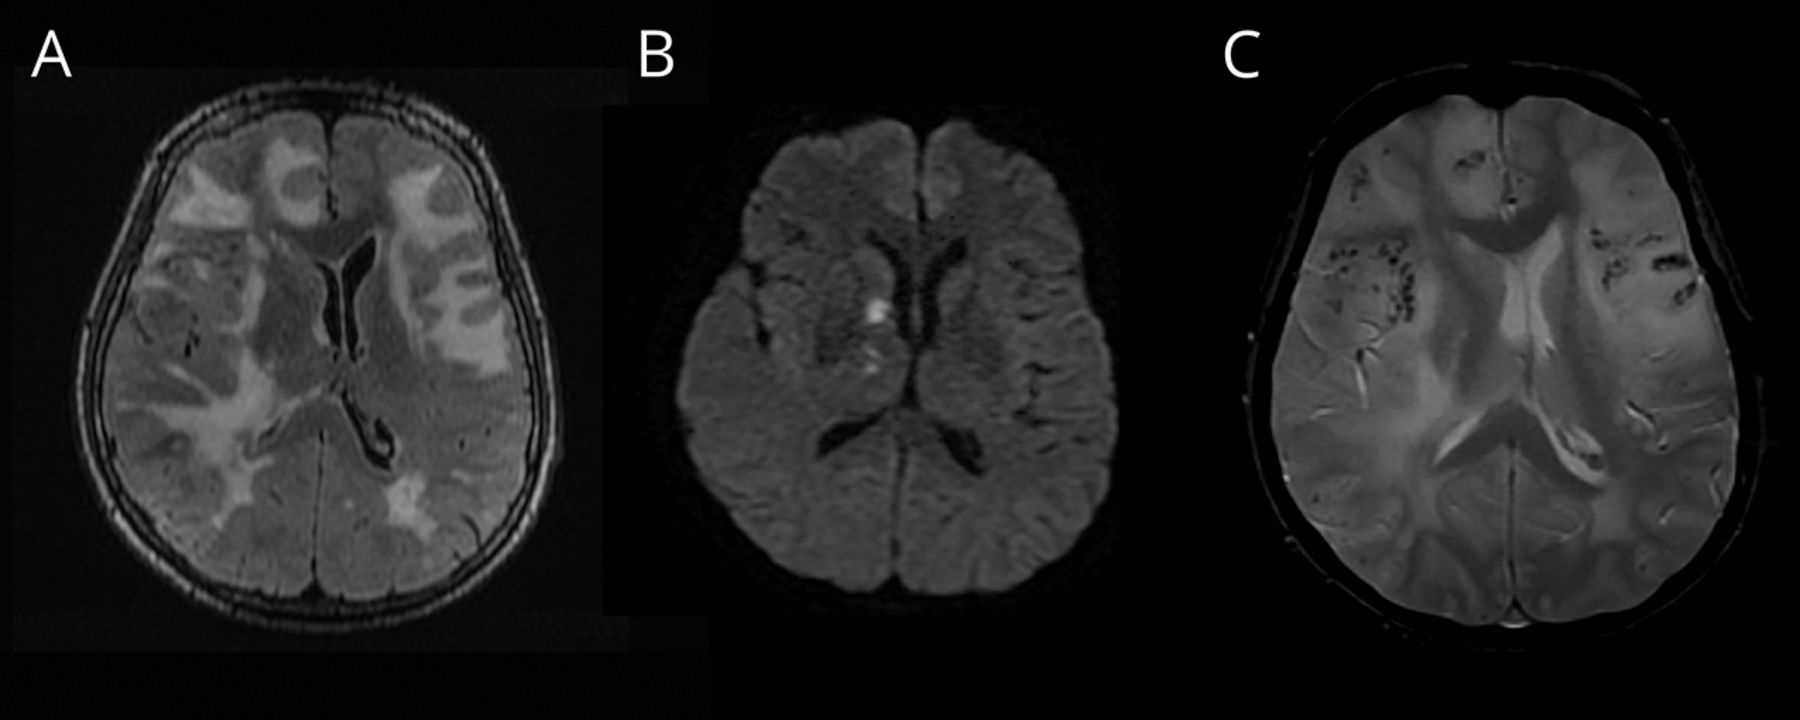

一个减轻以往健康的60岁的女人插管头痛和个月历史的帷幕,历史的记忆丧失。MRI进行(图1)。数字减影血管造影的头,水痘一带状疱疹病毒PCR,免疫球蛋白G CSF,肝炎B / C, CSF隐球菌抗原,艾滋病毒、莱姆血清学和梅毒屏幕是负的。最初的鉴别诊断包括中枢神经系统血管炎和颅内淋巴瘤。她被诊断出患有炎症基于clinicoradiologic标准脑淀粉样血管病(敏感性为82%,特异性为97%),1梗死认为amyloid-β-related脉管炎亚型。几天之内的类固醇,她完全清醒,重复MRI 5个月后显示改善脑白质病(图2)。蒙特利尔认知评估分数23/30开始后的两周治疗和22/30 5个月后。